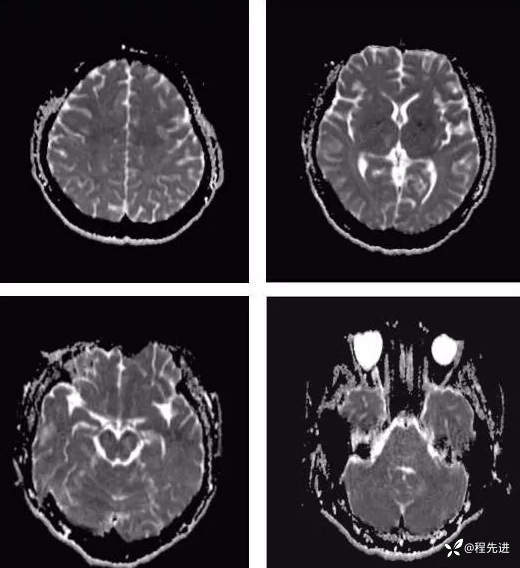

【神经】特别精彩病例|发热、头痛20天

病史:患者20天前无明显诱因下出现畏寒、发热,热峰39.5℃,热型不规则,不伴咽痛,流涕,感头昏,有头痛,阵发性加剧,伴呕吐,为胃内容物非喷射性。患者在外院查头颅CT示:未提示异常。外院予以“头孢类、退热药”,无明显好转。我院急诊予以“泼尼松,热毒宁"治疗无明显好转

外院胸部CT:两肺弥漫分布结节斑片影,考虑感染